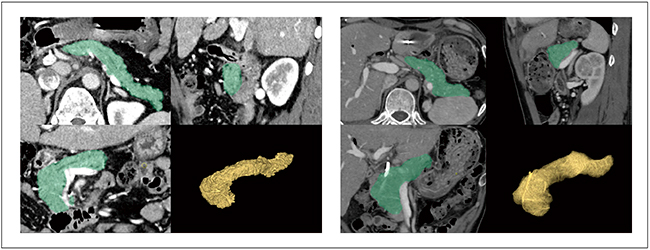

膵臓は,後腹膜腔に属しているため体内の深部に位置し,また,腹部大動脈や腸管を栄養する上腸間膜動脈,肝臓を栄養する固有肝動脈・門脈など,臓器を栄養する重要な血管と近接していることもあり,高難度の手術手技に区分される。そのため,術前に病変部を中心とした解剖学的情報の把握のため,3D表示の作成が求められることがある(図1)。

図1 膵臓を中心としたシミュレーション画像例

鏡視下シミュレータでは,動脈,静脈といった脈管系や脾臓,主膵管なども半自動,手動で抽出して合成表示することが可能である。